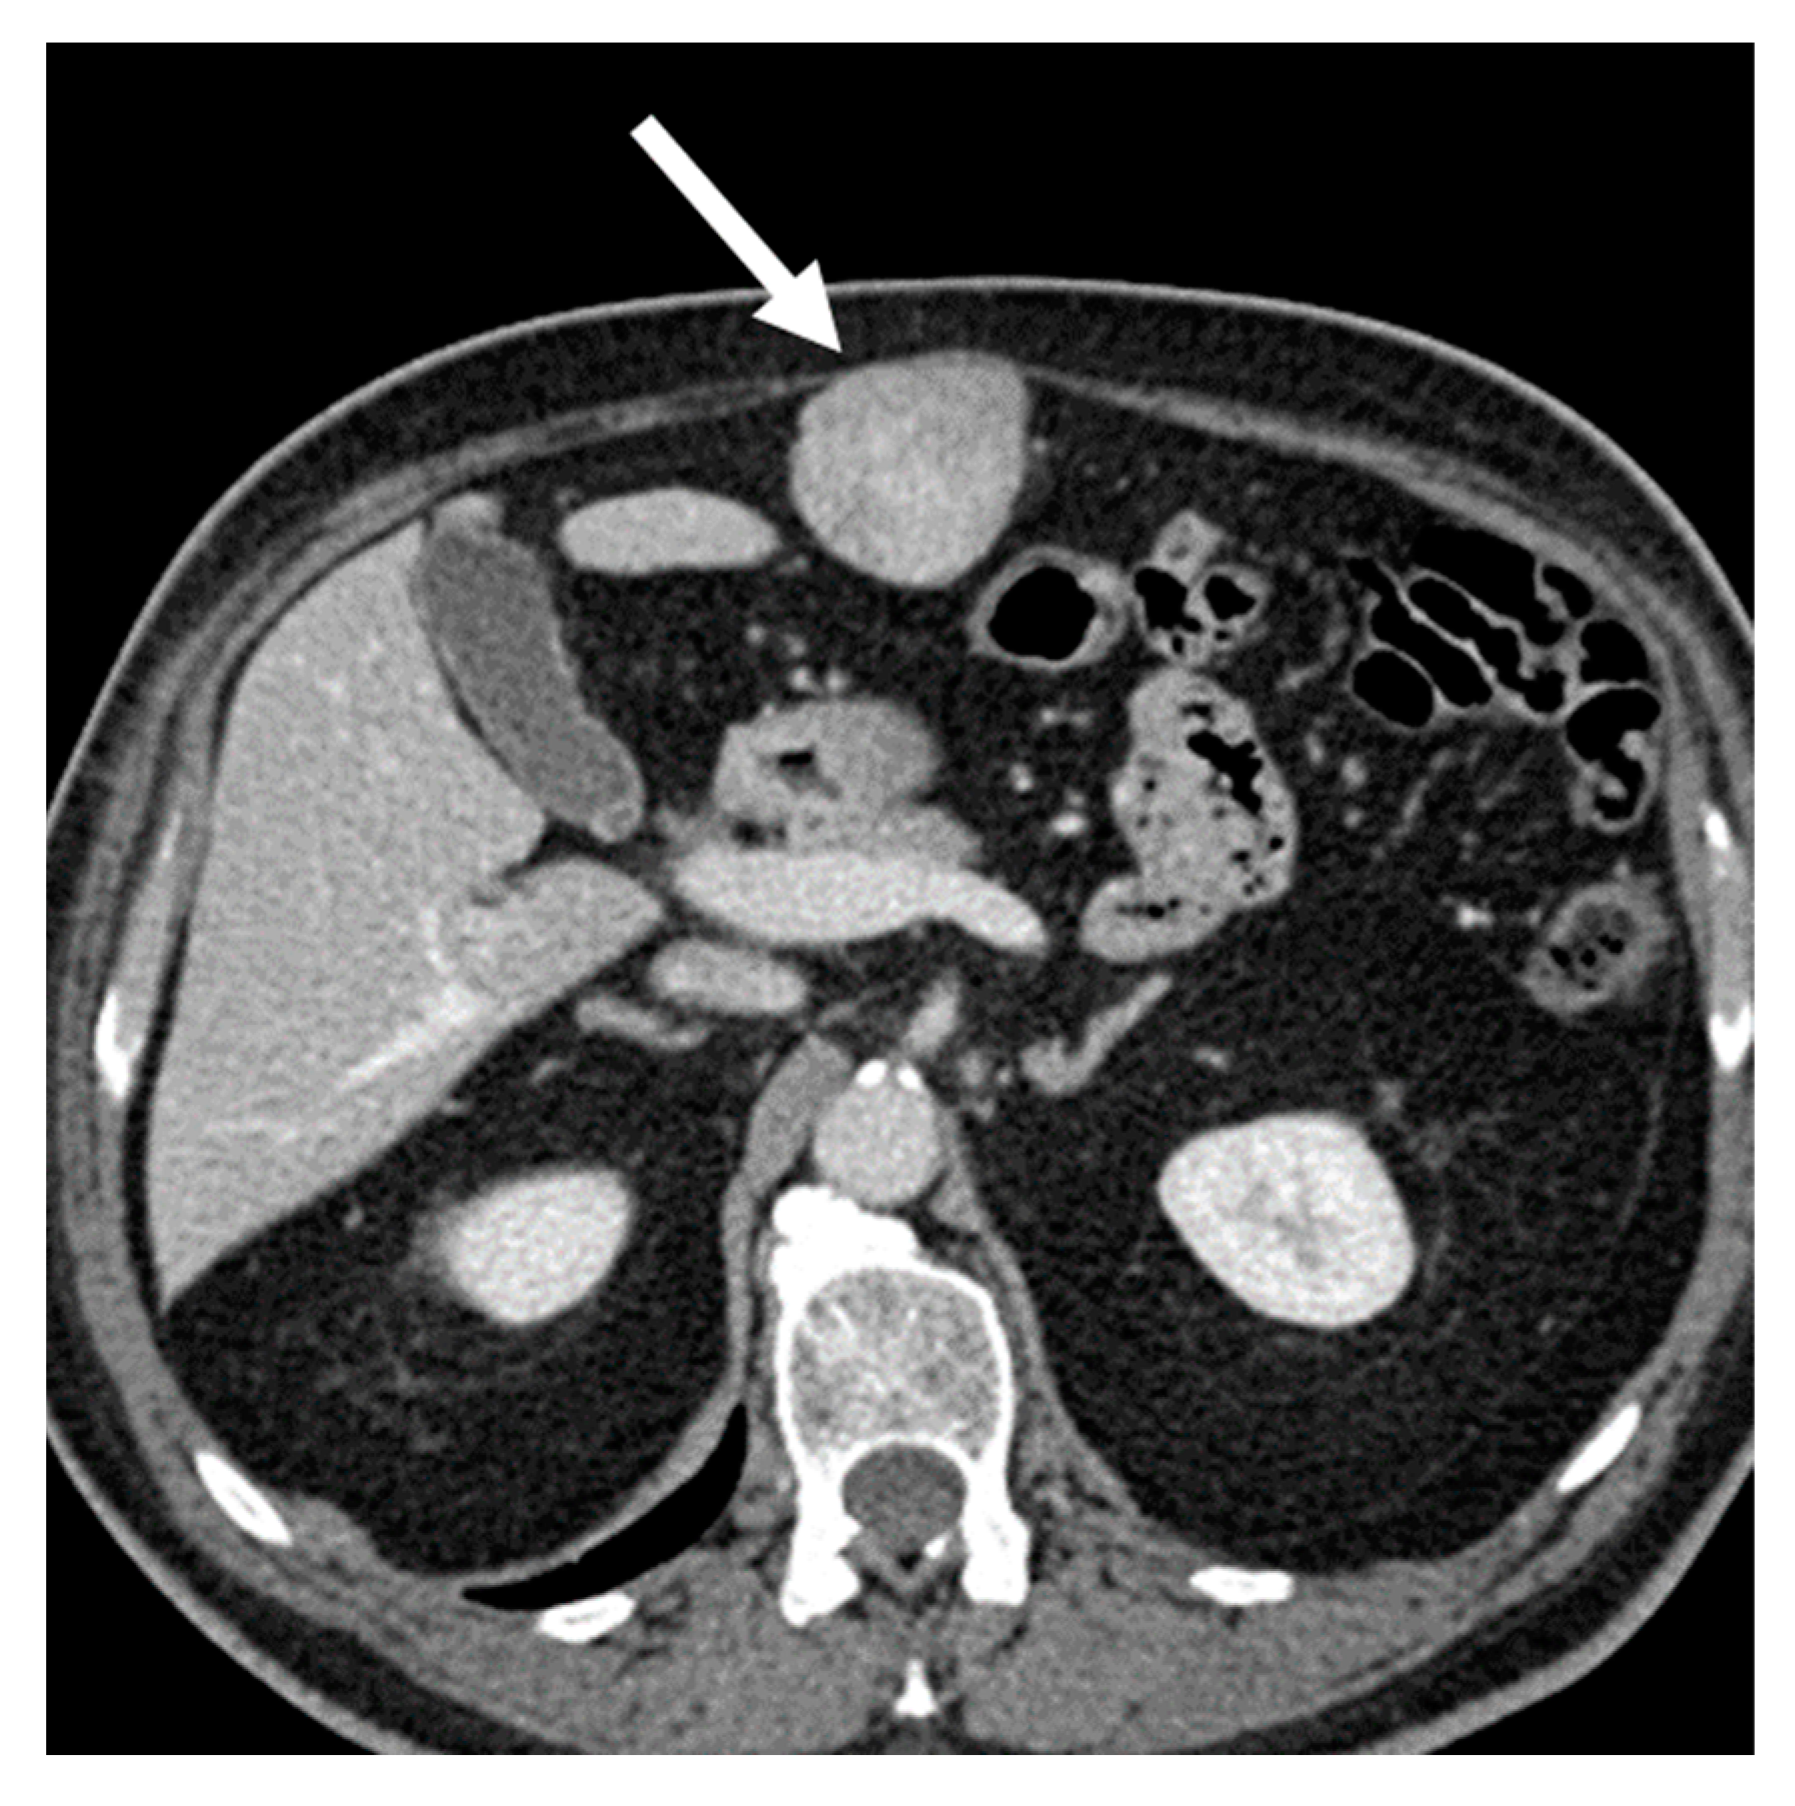

- Dedifferentiated liposarcomas (Figure 2) are high-grade tumors with poor prognosis. Characteristic features include heterogeneous nonlipomatous mass within, adjacent to, or surrounding a fatty mass [37,38]. There may be no evidence of fat-density tissue in up to 20% of cases, making the imaging diagnosis difficult [40]. Enhancing septa within the fatty portions are frequently seen [37]. Calcifications are rare (around 25% of cases) and are poor prognostic factors [39].

Figure 2. Dedifferentiated retroperitoneal liposarcoma in a 68-year-old man. Axial (A) and coronal (B) contrast-enhanced CT images in the venous phases show a 24 cm solid mass in the right retroperitoneal space, with internal necrotic areas and adjacent nodules (arrows). The lesion was histologically confirmed at biopsy.